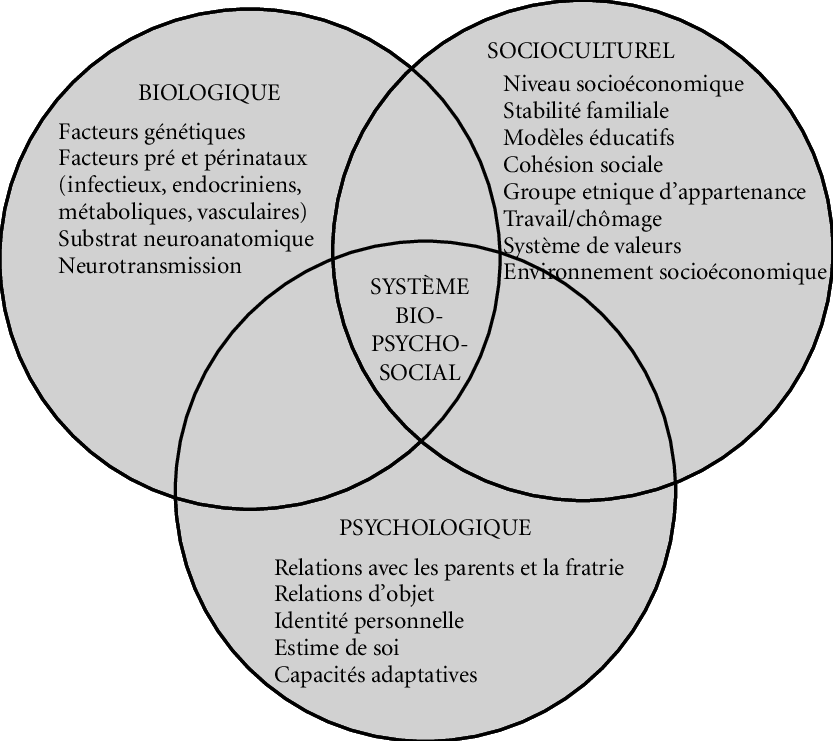

Le podologue est un professionnel de santé spécialisé dans l’étude, la prévention, le diagnostic et enfin la prise en charge et le traitement des affections du pied. La podologie est constituée de 2 branches distinctes mais complémentaires.

La première branche est centrée sur les problèmes unguéaux et cutanés: les ongles incarnés, les mycoses, les verrues, le suivi des personnes diabétiques (contrôle de la sensibilité, de la mobilité, de la peau et des ongles), la modification de la position des orteils grâce à la confection d’orthoplasties (orthèses en silicone réalisées sur mesure), la modification de la courbure des ongles via la mise en place d’orthonyxies (bridges de l’ongle permettant de le redresser et de supprimer les conflits.)

La deuxième branche de la podologie concerne la biomécanique: de manière pratique, elle traite les troubles de la marche, de la course, les problèmes posturaux, l’analyse des muscles et des ligaments en relation avec le pied, les pieds plats/ creux, etc. Celle-ci permet de mettre en relation différentes pathologies du pied avec des segments sous-jacents du corps (genoux, hanches, colonne vertébrale).

Lors de la consultation, le podologue effectue une anamnèse complète, un examen palpatoire des muscles et des ligaments, une analyse de la posture et de la marche. De plus, le podologue définit un traitement sur-mesure et réalise des semelles podologiques adaptées à la pathologie.